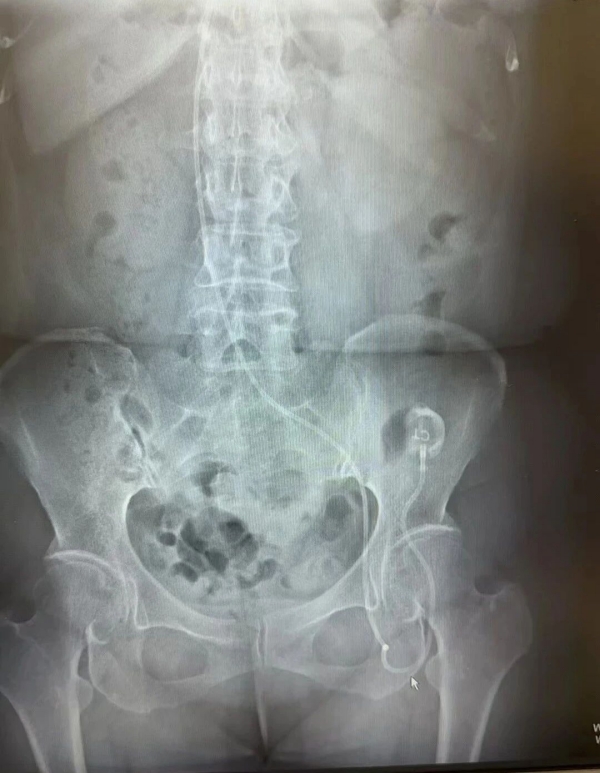

4特殊情况——股静脉输液港

当上述路径均受阻时,我们也可以选择经『股静脉』置入输液港。这里的解剖标志明显(腹股沟区的股三角内),容易穿刺进针;但由于部位靠近会阴区,感染风险高,因此不做首选。

▲ 经股静脉植入输液港

✦特殊情况下,如锁骨下静脉、颈内静脉、腋静脉等入路均受阻时,可选择『经股静脉』置入输液港。